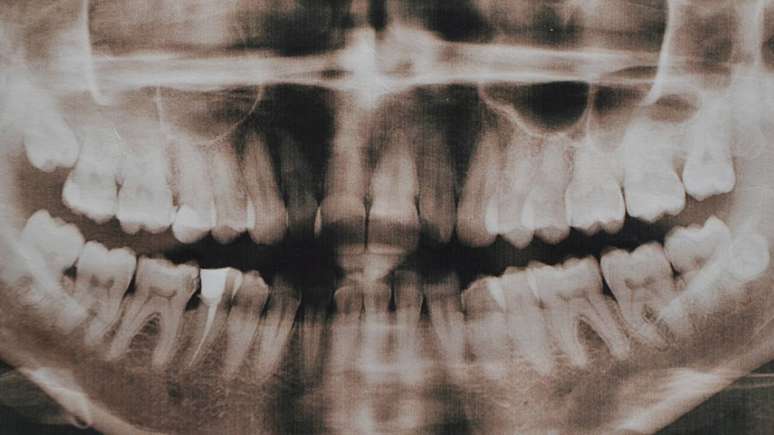

Alguns sinais podem levar profissionais de saúde bucal a suspeitar de hiperdontia, como atraso prolongado para a troca dos dentes de leite, presença de dentes muito próximos uns dos outros, dentes em posição incomum ou inchaço persistente na região da mandíbula ou maxila – depositphotos.com / alfexe

Alguns sinais podem levar profissionais de saúde bucal a suspeitar de hiperdontia, como atraso prolongado para a troca dos dentes de leite, presença de dentes muito próximos uns dos outros, dentes em posição incomum ou inchaço persistente na região da mandíbula ou maxila. Em cenários como esses, exames de imagem são fundamentais para identificar dentes supranumerários ou massas associadas, como os odontomas.